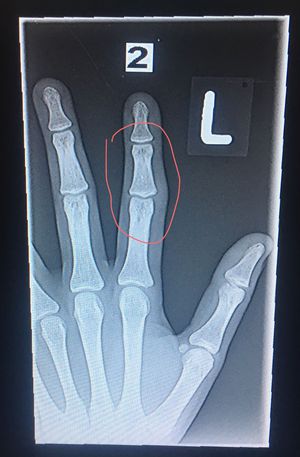

Broken finger?

Hi guys, can you tell me if there is a bone fracture, or something else? Please answer as fast as you can. Thanks

May be it is a hairline fracture in the phalangeal bone